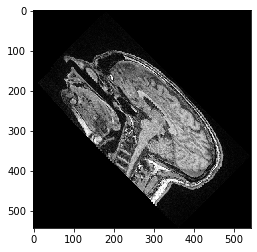

Nota: Si escalas primero y rotas después, o si rotas primero y escalas después, hace una diferencia:

transform = cle.AffineTransform3D()

transform.rotate_around_z_axis(rotation_angle)

transform.scale(scale_x=scale_factor)

cle_translated2 = cle.affine_transform(image, transform=transform, auto_size=True)

cle.imshow(cle_translated2[100])